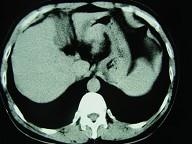

男,52岁,中上腹痛,影像检查如图,最可能的诊断是()A.慢肥厚性胃炎B.胃癌C.胃溃疡D.胃平滑肌瘤E.胃平滑肌肉瘤

问题 男,52岁,中上腹痛,影像检查如图,最可能的诊断是()

选项 A.慢肥厚性胃炎 B.胃癌 C.胃溃疡 D.胃平滑肌瘤 E.胃平滑肌肉瘤

答案 D